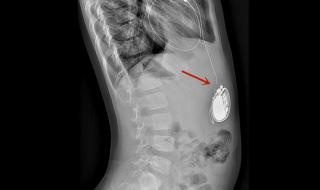

全磁浮人工心脏介绍 男子植入最小人工心脏

一、全磁浮人工心脏介绍

全磁浮心脏即离心泵人工心脏,被称为第三代人工心脏,是目前最先进,对人体影响最小也是最耐用的人工心脏,美国FDA前两年刚上市了第一款,我国高端医疗器械几乎无国产产品。